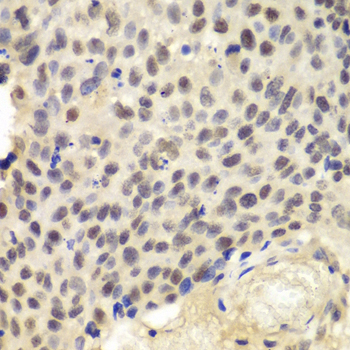

Immunohistochemistry of paraffin-embedded human esophageal using KPNA1 antibody at dilution of 1:100 (400x lens).